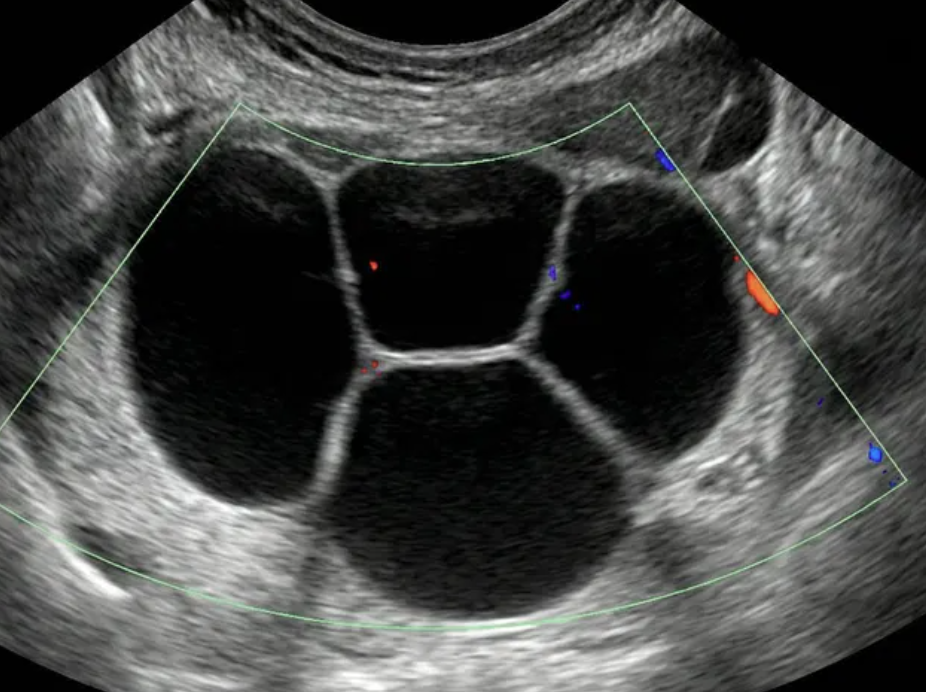

As regras simples do IOTA são um sistema de classificação baseado em características ultrassonográficas específicas que ajudam a distinguir massas anexiais benignas de malignas.

Classificação Benigna: Quando apenas regras benignas estão presentes (uma ou mais).

Classificação Maligna: Quando apenas regras malignas estão presentes (uma ou mais).

Classificação Indeterminada: Quando nenhuma regra está presente, ou quando há presença simultânea de regras benignas e malignas.